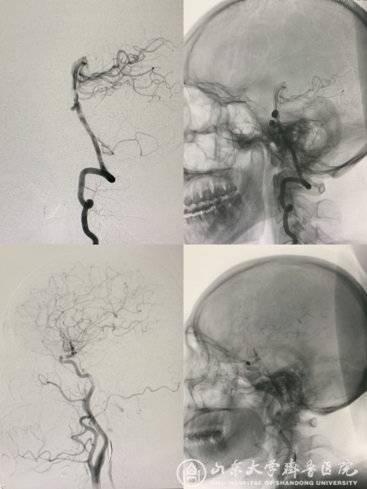

图-1两例脑动脉瘤栓塞术后日间手术复查造影,图像清晰,完全满足诊断需要。